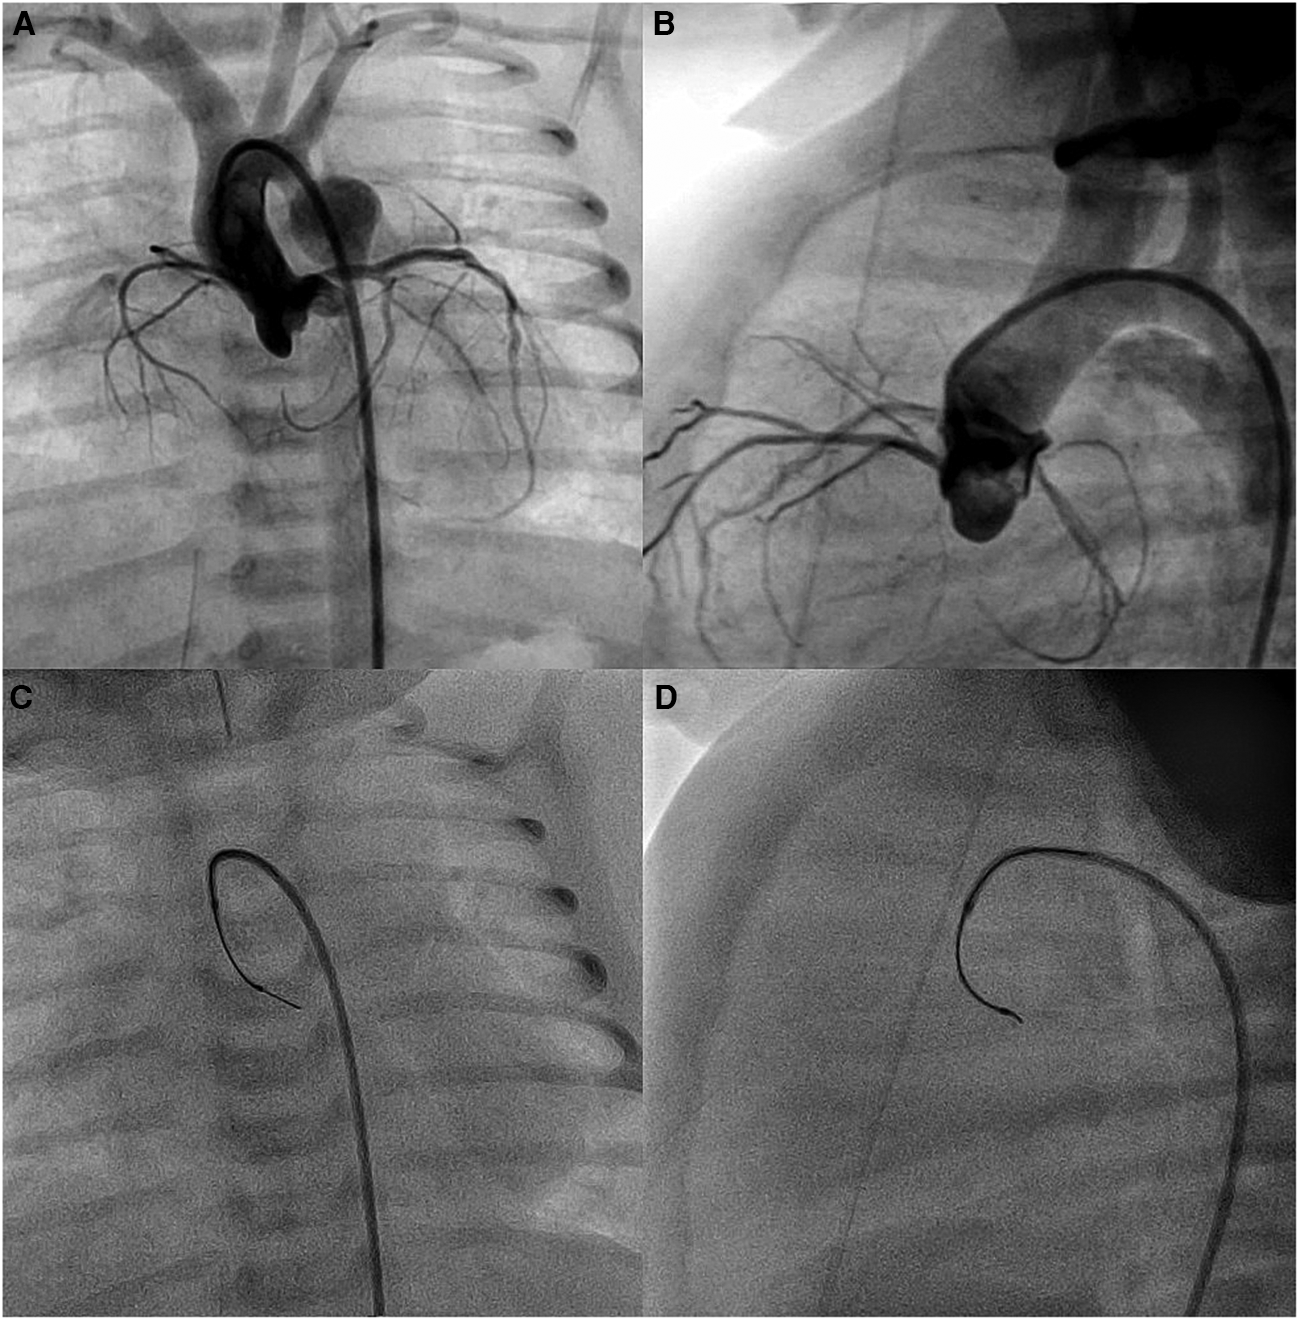

The cardiac catheterizations were transarterial in 36.8% of patients and interventional in 78.9% of patients. In three patients (no. 3, no. 12, and no. 15), the SwiftNINJA was applied upfront for precise cannulation of the right pulmonary artery and subsequent pulmonary flow restrictor implantation (Figure 2). In the other 16 patients, SwiftNINJA was applied after a median of 5 (IQR, 5–7) failed catheterization attempts using various combinations of catheters, microcatheters, and wires to rapidly cannulate challenging vasculature in seven, engage the lumen of stented vessels in five, cross complex aortic valve stenosis in three, and cross an apical ventricular septal defect in one.

FIGURE 2

www.frontiersin.org

Figure 2. Patient no. 13. SwiftNINJA is articulated precisely to cannulate the origin of the right pulmonary artery opening (white pointed arrow) to make sure that the wire will not touch the proximal part of the freshly implanted left pulmonary flow restrictor (black pointed arrow) (A,B). Precise implantation of bilateral pulmonary flow restrictors (Blue pointed arrows) (C,D).

We employed the SwiftNINJA upfront after baseline non-selective angiography to cannulate accurately, in one single attempt, a tricky right pulmonary artery and subsequently implant a microvascular plug-based bespoke pulmonary flow restrictor without touching the freshly implanted pulmonary flow restrictor in the left pulmonary artery (13). This eliminates the risk of mobilizing the left pulmonary flow restrictor in case the left pulmonary artery is cannulated unintentionally using standard pre-shaped hardware.

In this study, we showed that SwiftNINJA SM was applied successfully in various anatomical scenarios for efficient super-selective catheterization and subsequent interventional procedures in children with CHDs. The inherent ability of SM to access smaller vascular lumen makes these devices an interesting choice when performing pediatric interventions. Articulating the tip to the same angle as the aortic valve plane helped us to advance the guidewire and the SwiftNINJA through the stenosis, avoiding excessive wire manipulations and the associated valvular trauma. This feature was also helpful in crossing smoothly an apical trabeculated ventricular septal defect and in navigating unusual tortuous intra-cardiac routes to access the arterial ducts from the venous side, thereby avoiding larger arterial introducers. The 3D steering function facilitates maneuvers across endovascular stents, to accurately cannulate the lumen without engaging the struts or to catheterize challenging jailed branches by crossing the correct struts (22). During bilateral implantation of pulmonary flow restrictors, the anatomy and angulation of the pulmonary bifurcation can be tricky sometimes. We don't want to take any risks after implanting the left pulmonary flow restrictor to have the wire going by mistake to the left pulmonary artery which can dislodge or affect the configuration of the freshly implanted left pulmonary flow restrictor, especially when the mouth of the device is a bit sticking out (13). Therefore, we think that SwiftNINJA SM can be used upfront to anticipate increased procedural time, contrast material, and radiation exposures concerning tricky vascular anatomies.